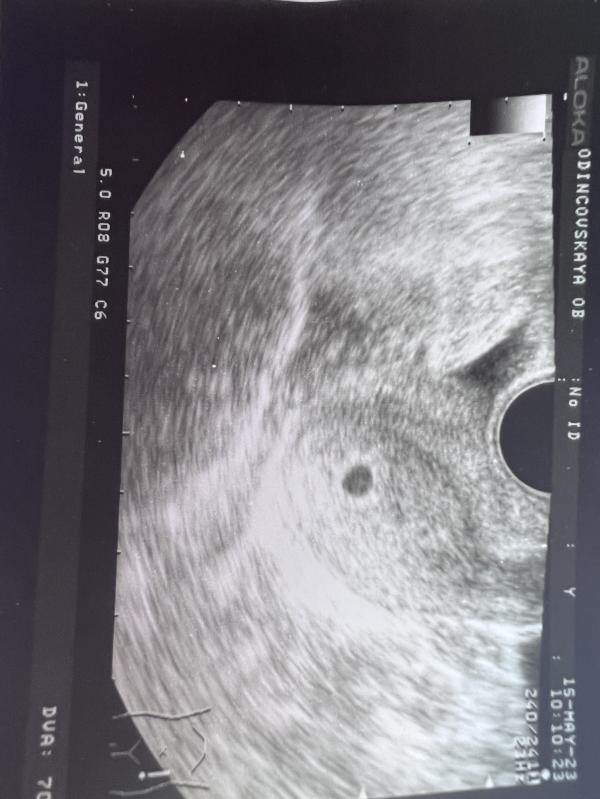

Беременность 5.4 недели

Была на узи, все отлично, малыш развивается)

Уже 5.4 недели, даже не верится как то